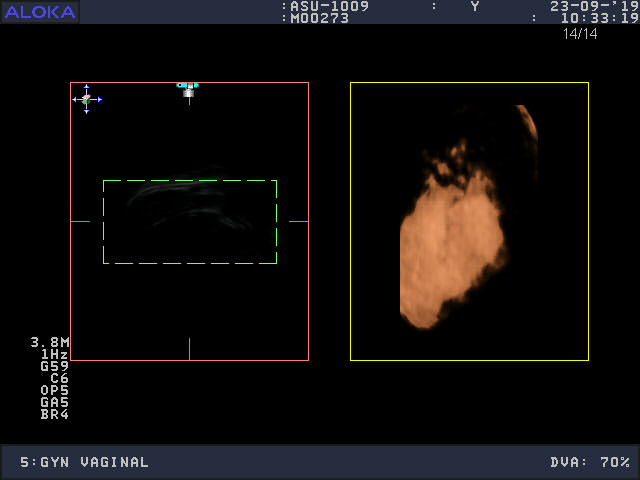

Aloka ASU-1003 Ref 3D/4D Vaginal – ProSound

Aloka Vaginal ASU-1003 3D/4D

Intended use

Volume Obstetric and Gynecology

Aloka ASU-1003 3D/4D Vaginal – ProSound

Frequency Range: 9 – 3 MHz

Scan Width: 9 mm Radius

Scan Angle: 163° FOV

Prosound Connector

Aloka ASU-1003 3D/4D Vaginal – ProSound for Volume Obstetric and Gynecology